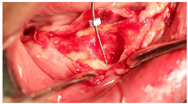

(4)下颌拔牙后4个月(2016年1月)复诊,口腔CBCT检查43、44区骨组织早期愈合(图7),牙槽嵴顶黏膜愈合良好(图8A),口腔局部阿替卡因肾上腺素注射液浸润麻醉,32、42区轴向植入Nobel Speedy4 mm×13 mm种植体,35区斜行植入Nobel Speedy4 mm×15 mm种植体,43、44区骨组织愈合不良,清理肉芽组织后呈凹坑型骨缺损(图8B),45区倾斜备洞穿越44、43骨缺损区植入Nobel Speedy4 mm×18 mm种植体(图8C),4颗种植体初期稳定性均达到35 N·cm,安装复合基台。43、44骨缺损区回填自体骨屑(图8D),修整牙龈、黏膜瓣复位,4-0可吸收缝线严密缝合创口。术后即刻制取印模,制作下颌种植固定过渡义齿并戴入,义齿修复到第二前磨牙,建立上下颌固定义齿咬合关系。(图9)。